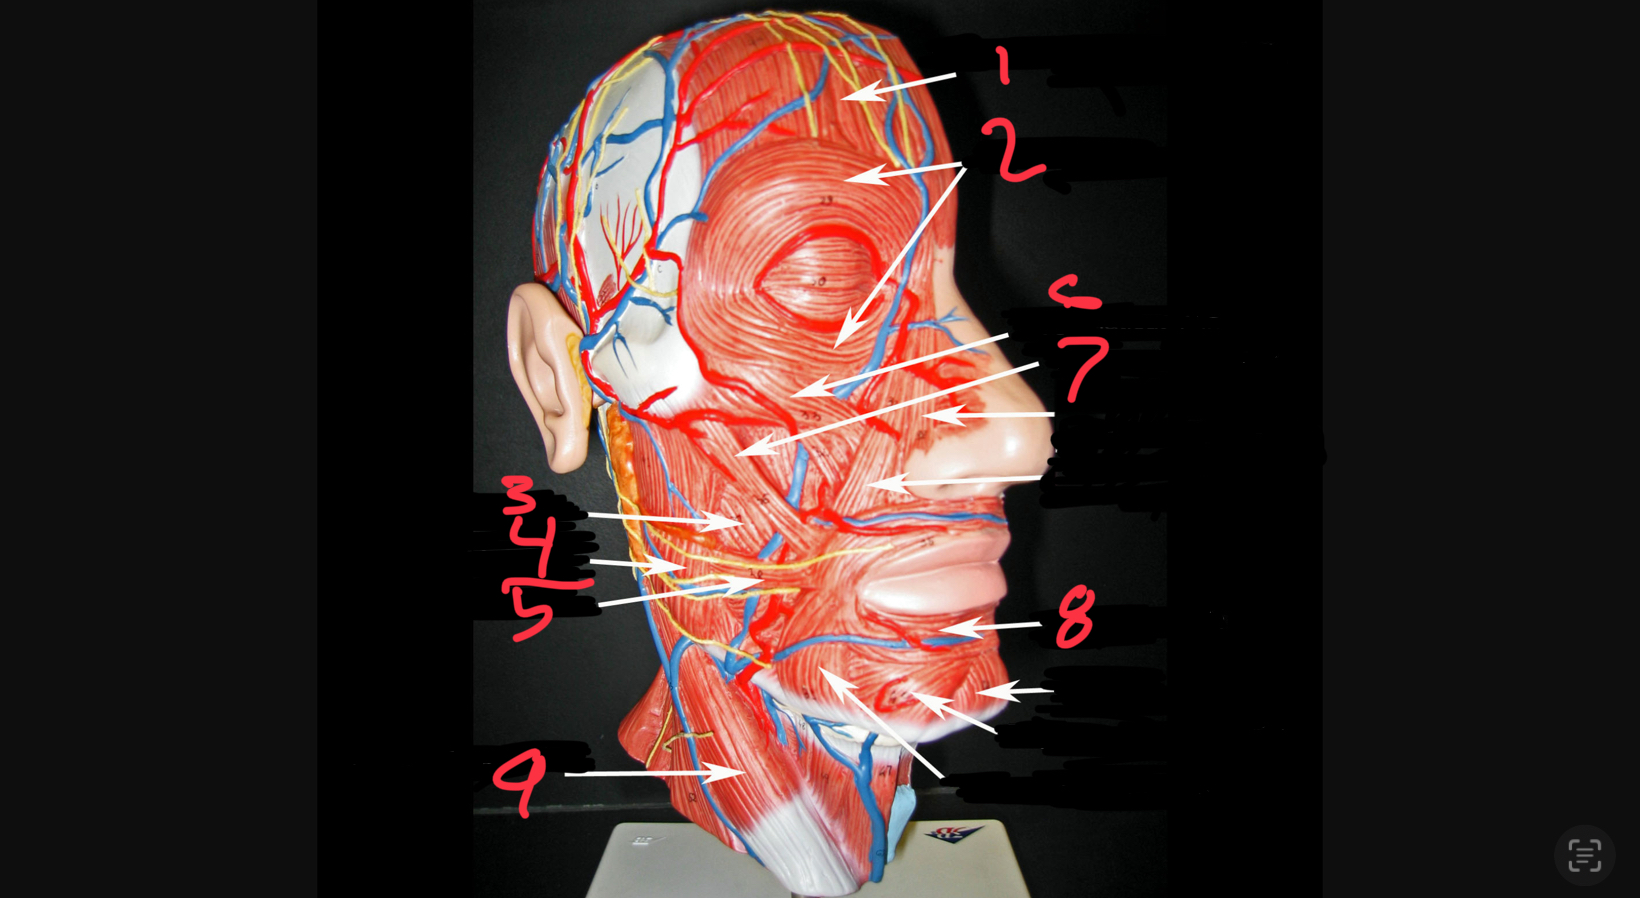

what #1

occipitofrontalis (frontal belly)

what is #2

orbicularis oculi

what is #3

buccinator

what is #4

masseter

what is #5

risorius

what is #6

zygomaticus minor

what is #7

zygomaticus major

what is #8

orbicularis oris

what is #9

sternocleidomastoid